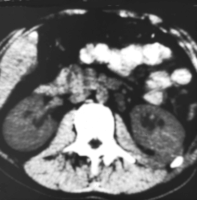

Von Wichtigkeit sind die bildgebenden Verfahren: Sonographie, CT bzw. AUR.

Beispielhaft die Darstellung eines ausgedehnten Nierenabszesses in Sonographie, CT und AUR (Abbildung 6).